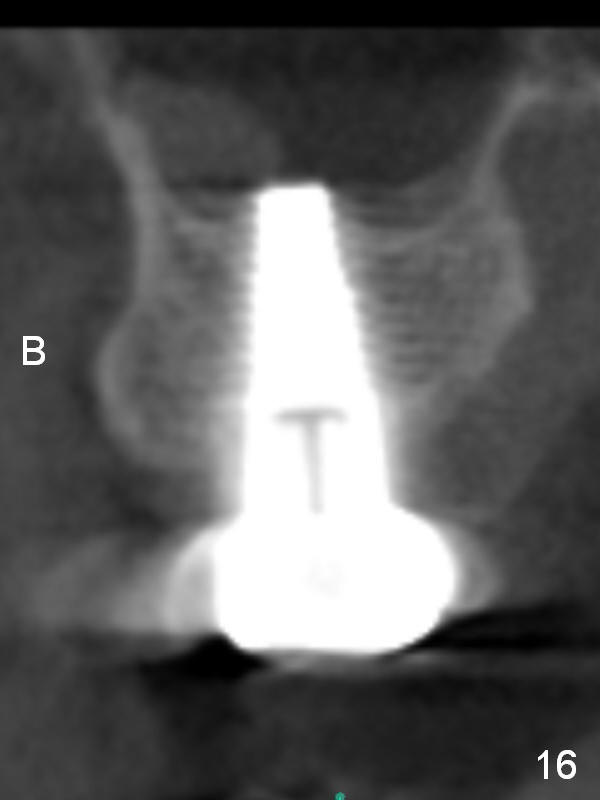

The implant remains stable 2.5 months postop without abnormal bone resorption (Fig.9). Since the provisional has dislodged on several occasions, impression is taken for final restoration. When the provisional is removed 3 months postop, the margin of the restoration is shown to be subgingival (Fig.10 arrowheads), but is distinctly separated from the gingiva. This is due to the presence of the provisional (its margin were fabricated slightly deeper). The provisional is also intentionally fabricated slightly larger than the final restoration. When the latter is cemented, there is space to remove extra cement trapped subgingivally (Fig.11). No cement is visible post cementation (Fig.12 (C: crown)). Eighteen months post cementation, the patient returns for recementation. After laser gingivectomy and Panavia resin bonding, PA shows residual cement (Fig.13 ^). After repeated removal with Piezo scaler and explorer, the residual cement appears to be smaller, which is ignored at the time of X-ray taking (Fig.14 ^). More dismayed is tight mesial contact. Water pik is recommended. When peri-implantitis develops later on, make an incision for cement removal. If the crown is dislodged soon, check whether the existing abutment is loose, remove acrylic in the access hole and remove the abutment. Install a new 4x3 mm one. Trim the abutment carefully and more on the opposing tooth.

CBCT taken 23 months post cementation shows no abnormality (Fig.15-17). On the contralateral side, the apex of the tooth #15 is immediately inferior to the sinus floor (Fig.18 (sagittal section), 19 (coronal section)). The immediate implant seems to be unavoidably entering the sinus. The implant seems to be normal 3 year 5 months post cementation.